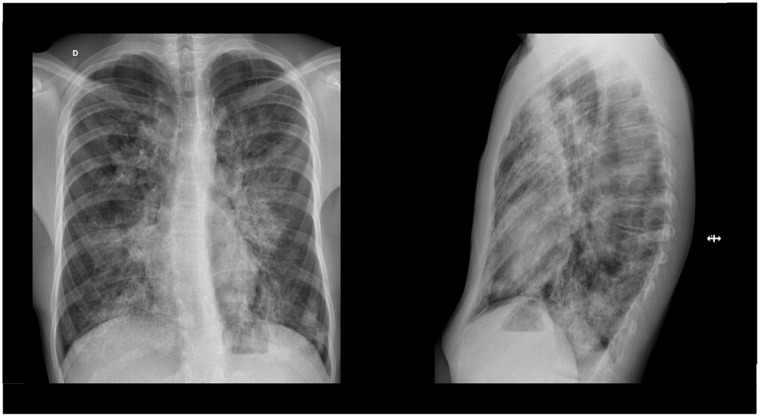

Autoimmune pulmonary alveolar proteinosis (AI-PAP) is a rare condition, especially in children. The clinical presentation ranges from asymptomatic forms to respiratory distress requiring ventilation. We describe the case of a 13-year-old adolescent male who presented to the emergency department with acute pleuritic chest pain not associated with systemic complaints. On examination, he had diminished breath sounds in the lower two thirds of the chest with no other abnormal findings; SpO2 (oxygen saturation) was 98% on room air. Chest radiograph revealed a marked interstitial infiltrate, comparable with the one taken 4 years earlier during an acute illness that was presumptively treated with azithromycin. A computed tomography (CT) scan revealed multiple bilateral areas of ground-glass opacities with areas of crazy paving, involving > 65% of lung parenchyma, suggestive of pulmonary alveolar proteinosis (PAP). Respiratory viral testing, including for coronavirus (SARS-CoV2), was negative. Bronchoalveolar lavage performed in the outpatient setting revealed a milky fluid and positive periodic acid-Schiff staining. Spirometry indicated a mild restrictive pattern (forced vital capacity [FVC] = 77%) and diffusing capacity of the lungs for carbon monoxide (DLCO) showed a moderate decrease at 48.6%. No mutations associated with surfactant dysfunction were found on the genetic panel. Anti-granulocyte macrophage colony-stimulating factor (GM-CSF) antibody testing was strongly positive, raising suspicion for autoimmune PAP. At 20 months of follow-up, the patient remains asymptomatic with a normal spirometry. Although treatment with agents, such as the inhaled form of granulocyte-macrophage colony-stimulating factor (GM-CSF) appears promising for the treatment of symptomatic adult patients, as this patient remains asymptomatic, a conservative approach was taken, and he continues to be monitored in the clinic.